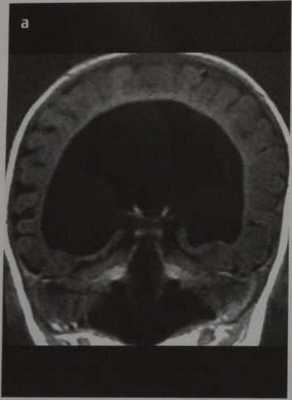

Семилобарная голопрозэнцефалия. МРТ, Т1 -ВИ во фронтальной плоскости. Визуализируются рудиментарные височные рога боковых желудочков, неполный гиппокамп, частично разделенные таламусы, отсутствие прозрачной перегородки.

Семилобарная голопрозэнцефалия:

- Продольная щель

- Имеются задние рудименты серпа большого мозга

- Лобный отдел мозга недоразвит и не разделен

- Таламусы частично разделены

- Рудиментарные височные рога боковых желудочков

- Неполный гиппокамп

- Отсутствует прозрачная перегородка

- Ствол мозолистого тела отсутствует; валик имеется.